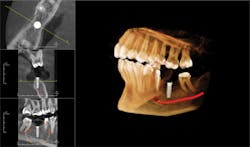

The OP300 Maxio offers extended fields of view for diagnosis and treatment of the entire maxillofacial region.

13x15 covers the entire maxillofacial region.

Larger fields of view offer broader diagnostic capabilities, including airways.

Selecting the precise area of interest is as easy as pointing.